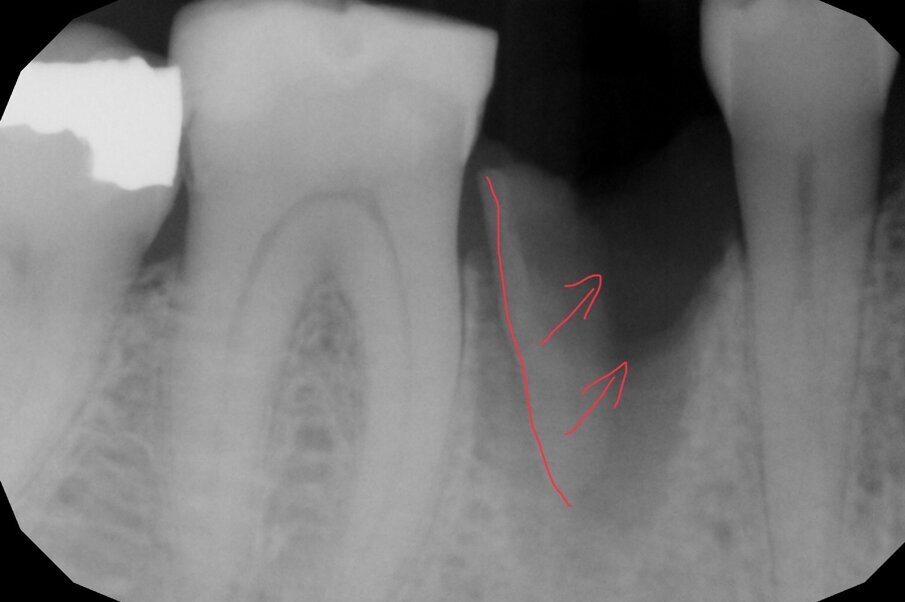

In questo caso clinico la difficoltà consisteva nel fatto che si è resa necessaria l’estrazione della metà mesiale della radice fratturata e quindi nel far compiere al frammento radicolare rimasto un movimento diagonale per mezzo del quale la porzione distale rimasta con il legamento parodontale avrebbe permesso una corretta rigenerazione tissutale ossea come indicato in rosso nell’immagine radiografica.